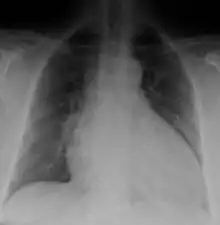

Dilated cardiomyopathy on CXR

Generalized enlargement of the heart is seen upon normal chest X-ray. Pleural effusion may also be noticed, which is due to pulmonary venous hypertension.[28]